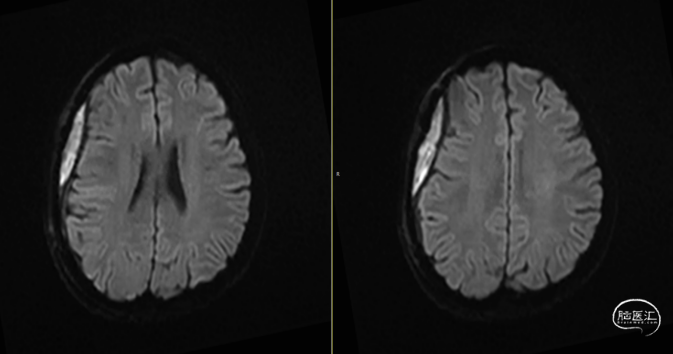

第2次术后12天,仍有间断头痛,刀口愈合可,复查颅脑MRI(如上图):右侧额顶颞部软组织稍增厚,右侧额顶部颅板下见条片状长T1、长T2信号,T2FLAIR呈稍高信号,边界清,DWI(b=1000)呈混杂高信号,相应ADC呈混杂高信号影,加用美罗培南联合万古霉素抗炎治疗。

第3次术后16天,复查颅脑MRI(如上图),硬膜外及皮下异常信号较前明显减少,负压引流管引流不明显,拔除负压引流管,继续使用头孢曲松+多西环素口服联合抗炎治疗。